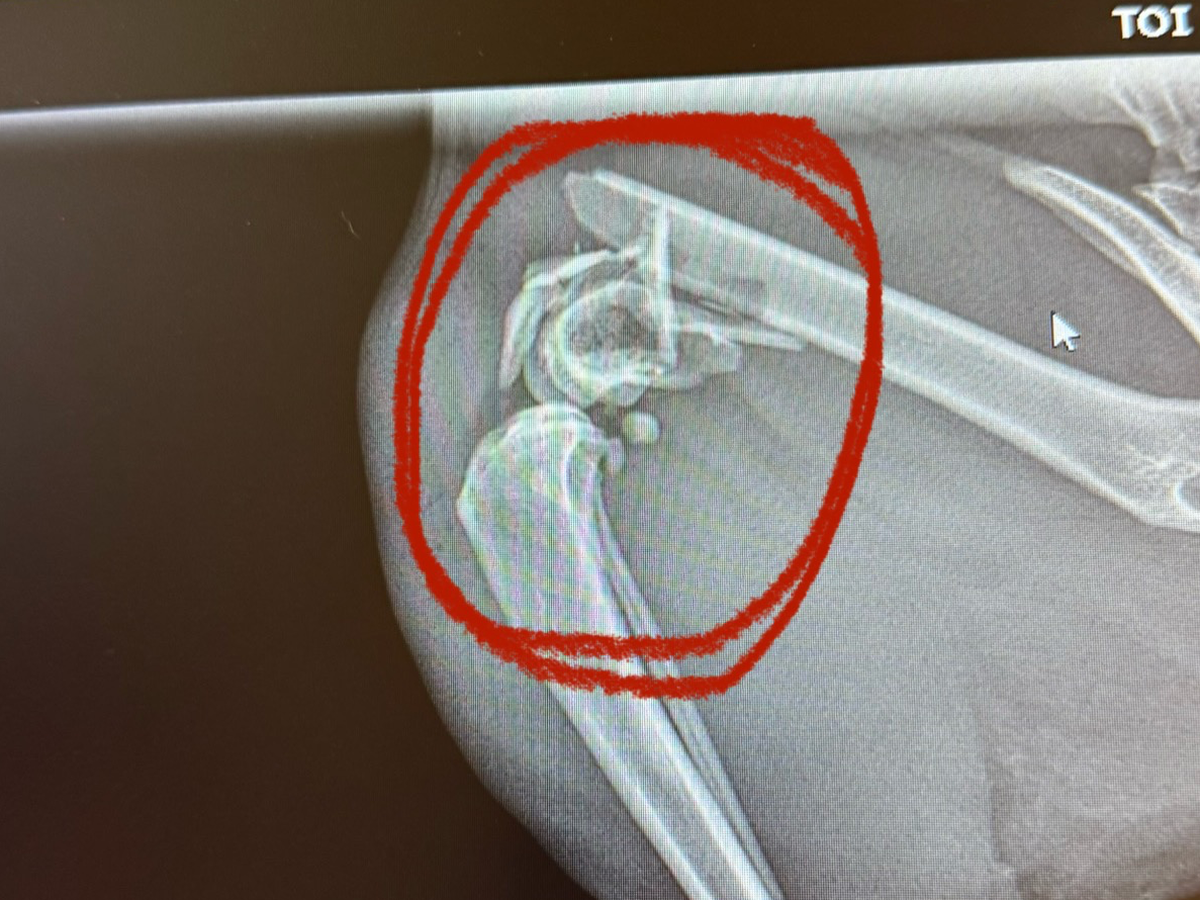

Hello everyone, I am needing YOUR help!!! This is our sweet boy Calcifer! Unfortunately, he will have to get his leg amputated due to his leg fracture. He has a comminuted fracture which is a more serious leg fracture that doesn’t just break clean, his bone broke into multiple pieces and if we were to get his surgery for his leg then it would be anywhere from $6k-$8k which we know we won’t be able to fund in time if he were to have the surgery. We have applied for Care Credit and hoping they accept us. It would really help us out in the long run if they were to accept us but for now we are trying our hardest to raise the funds for his amputation. They also told us If he were to have the surgery then there would be a 20% rate that he wouldn’t make it through and we rather not risk that 20% and they said if he were to have it then it could also still give him problems in the future, so amputation is our best option. His amputation treatment is $1,454 and so far the gofundme is really pushing it and i’m so very grateful for every dollar that has been sent for my sweet boy. We would like to get his amputation done next thursday! I genuinely am desperate and asking for anything anyone can give so my sweet boy doesn’t have to be in pain anymore. Please share with family members and on your social medias!! post the link as much as you can so this can reach where it needs to be!! anything genuinely helps!!